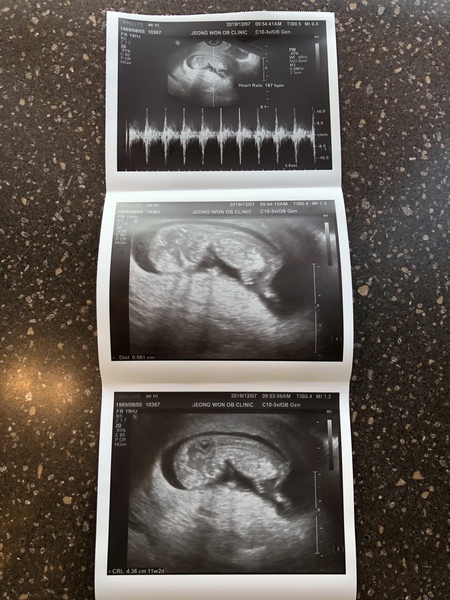

Hi, I’m new to this board although I’ve been lurking for weeks. I’m 11+3 today. Had the NT scan on Saturday and was measuring 11+2 which was a huge relief because we had some scares at the start with a subchorionic hematoma spotting. Both me and my husband are finally starting to feel this is real now, now that it actually looks like a baby.

Eventful weekend for me 🙈 started bleeding but it eased off had epu scan today

I’ve been put back two weeks as baby measuring 9weeks , two babies are there but sadly only one has a heartbeat

Hope everyone is well, it’s lovely seeing the scan photos coming up I’ve got another scan in two weeks x

Scan today went well. I was feeling pretty anxious and the 45 minute wait didn't help - but there is definitely a little wriggly bean in there, so lovely to finally see! I'm going to try to relax a bit now, and eat my veggies like a good girl Grin

We've got a scan at 7pm tonight.. feels like the day is dragging xx

12 week scan this morning, all looking good as far as they can tell at this stage! Just waiting for screening results to come back now. As soon as you get past one worry it’s on to the next hey! Dates were pretty much what I thought, just moved by a few days to 11+4 today, EDD 28th June. Been sick 3 times today so far and my toddler got up for the day at 4.30am SadEnvy

I had my scan today and they've said baby is measuring a week behind so I'm only 11 weeks but I'm so confused. I had a positive test on the 20th october and a digital positive on the 23rd october. I have another scan next Friday but I'm in panic mode thinking something just isn't right. My periods weren't very regular as only had two periods after coming off my pill so wouldn't know my cycles exact. Does this all sound normal?

Hi ladies sorry I've been quiet on here lately had my 12 week scan on Wednesday it was amazing anyone good at nub theory feel free to have a guess.

Due 20th June

13 weeks today

Hi all- I had my 12 week scan on Friday and thankfully all looked fine. For anybody anxious in the lead up to it, I hear you! Baby was not playing the game at all and kept turning away from the camera 🙄 Our scan picture sadly resembles very little of a baby 😂 All in all very happy though.